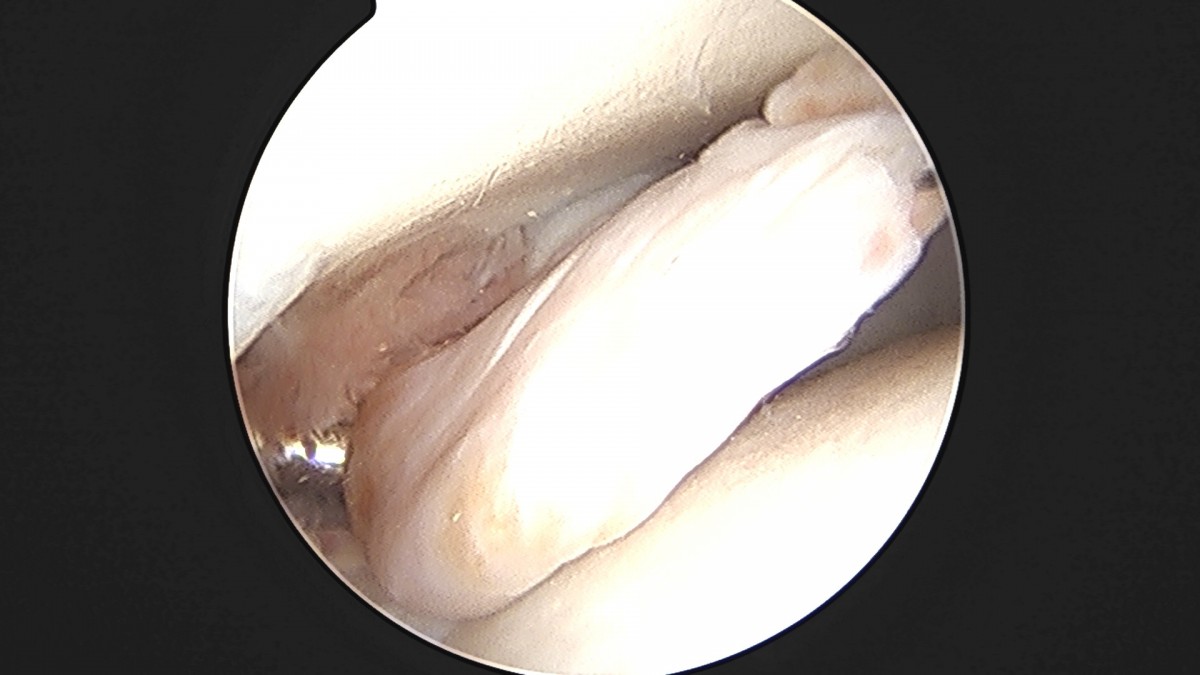

이재상원장님 발목 활액막 절제술 및 인대 봉합술 정보O 환자

dae765e4d9ac96aee867c9d6292d8784_1758003798_3741.jpg